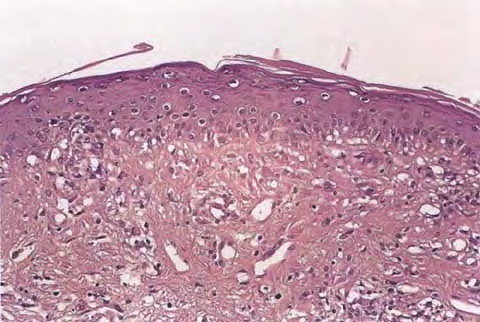

Histopathology. The erythematous-edematous lesions of the skin in dermatomyositis may show only nonspecific inflammation. However, quite frequently the histologic changes are indistinguishable from those seen in SLE. There is epidermal atrophy, basement membrane degeneration, vacuolar alteration of basilar keratinocytes, a sparse lymphocytic inflammatory infiltrate around blood vessels, and interstitial mucin deposition . With severe inflammatory changes, there may be associated subepidermal fibrin deposition. Although immune complexes are not detected at the dermal-epidermal junction as in lupus erythematosus, it should be

remembered that up to 50% of subacute cutaneous lupus biopsies can also have a negative direct immunofluorescence.

Old cutaneous lesions with the clinical appearance of poikiloderma atrophicans vasculare usually show a bandlike infiltrate under an atrophic epidermis with hydropic degeneration of the basal cell layer (see also the section on poikiloderma atrophicans vasculare). The Gottron’s papules overlying the knuckles also show vacuolization of the basal cell layer but acanthosis rather than epidermal atrophy . Subcutaneous tissue may show focal areas of panniculitis associated with mucoid degeneration of fat cells in early lesions. Extensive areas of calcification may be present in the subcutis at a later stage .